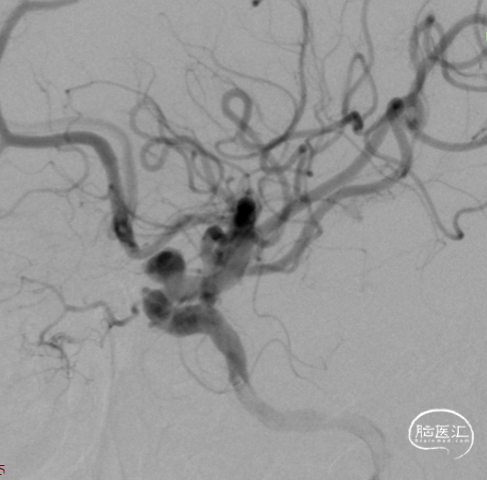

术前造影:

左颈。